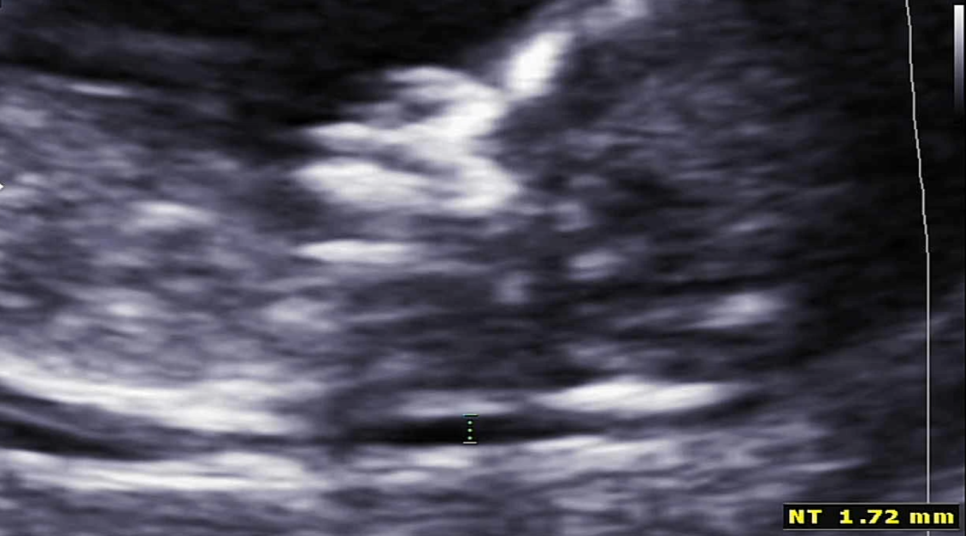

그리고 그 유명한 #목투명대 검사! 목투명대가 너무 두꺼우면 다운증후군과 에드워드 증후군이 있을 확률이 높대요 ㅠㅠ목투명대는 3mm를 넘으면 안된다고 하셨는데, 오토는 1.7mm로 통과했습니다 휴~